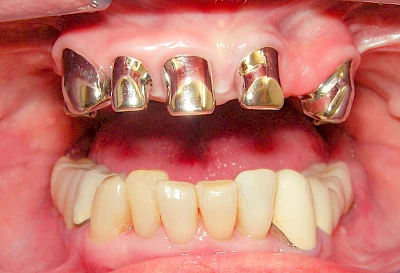

Bei herausnehmbaren Prothesen werden Implantate eingesetzt, um den Halt und den Tragekomfort der Prothesen zu verbessern. Dazu kommen verschiedene Verbindungselemente zum Einsatz:

- Teleskope

- Kugelköpfe

- Tellerförmige Lokatoren

- Stege

- Magnete (selten)

Neben rein implantat-getragenen zahnärztlichen Versorgungen werden bei herausnehmbaren Prothesen Implantate auch in Sinne einer "strategischen Pfeilervermehrung" ergänzend zu eigenen Zähnen zur Verankerung eines Zahnersatzes genutzt.

Varianten zur Verankerung von abnehmbarem Zahnersatz auf Implantaten